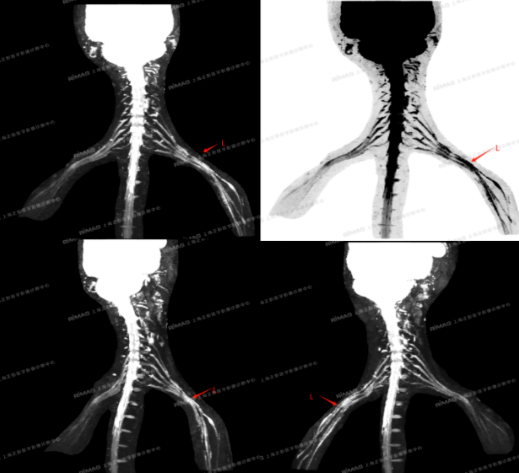

两侧C5-8、T1神经汇入两侧臂丛神经,显示清晰、对称,信号、形态未见明显异常,未见明显受压、中断改变。两侧臂丛神经显示清晰,右侧信号、形态未见明显异常,未见明显受压、中断改变;左侧臂丛神经连续,较对侧略增粗、信号增高,内、外侧束明显。

左侧臂丛神经增粗、信号增高,考虑损伤后改变。

专家们指出,影像清晰地显示了神经增粗和信号异常的范围与特征,这符合创伤后神经本身水肿、炎症反应的表现,同时也排除了因为术后疤痕组织增生、粘连并压迫神经的可能(如果是严重粘连压迫,影像上可能会有明显的受压变形或中断)。